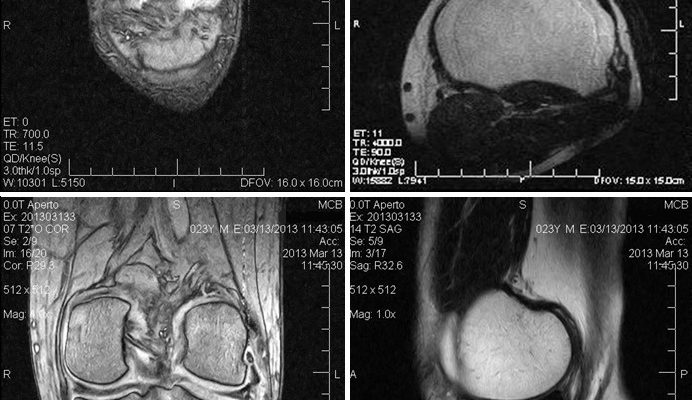

Магнитно-резонансная томография

В принципе, позволяет выявлять все то же, что и КТ. Исследование необходимо проводить, если требуется дифференциальная диагностика солевых отложений с новообразованиями. В этом плане равных по информативности МРТ методов нет.